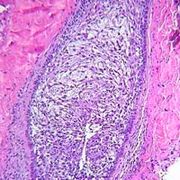

- 定义滴虫阴道炎(trichomonalvaginitis)由阴道毛滴虫引起,是常见的阴道炎。阴道毛滴虫适宜在温度25~40℃

滴虫性阴道炎是由阴道毛滴虫引起的一种阴道炎。患者症状主要是稀薄的泡沫状白带增多及外阴瘙痒,可伴有烧灼感、疼痛和性交痛。治疗方案有全身用药和局部用药。滴虫性阴道炎患者的丈夫或...